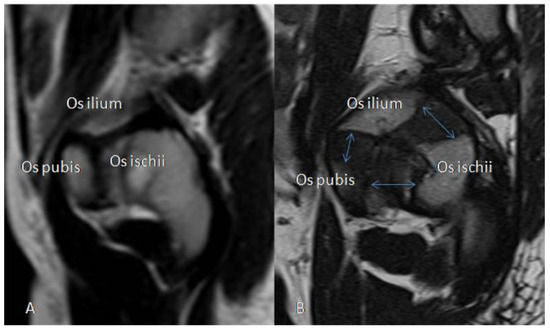

3.2.5. MRI